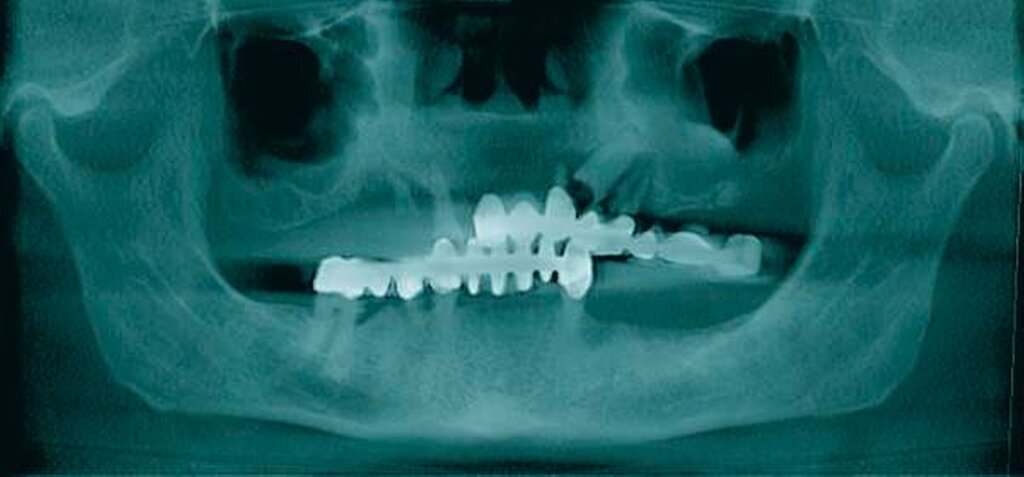

In der durchgeführten radiologischen Diagnostik zeigten sich ausgeprägte Parodontopathien mit Verdacht auf eine BRONJ bei gut begrenzter radiologischer Aufhellung mit Kieferhöhlenbeteilung (Abbildungen 3 bis 5). Unter der Verdachtsdiagnose einer BRONJ wurde somit die Indikation zur Zahnsanierung mit Exzision der pathologischen Veränderung im Oberkiefer gestellt. Nach Entfernung der gelockerten Brücke zusammen mit den die Brücke tragenden Zähnen zeigten sich große Mengen harten, anhaftenden Gewebes (Abbildung 6); der unter dem Befund liegende Knochen stellte sich klinisch als vital und ohne Anzeichen einer Nekrose dar.